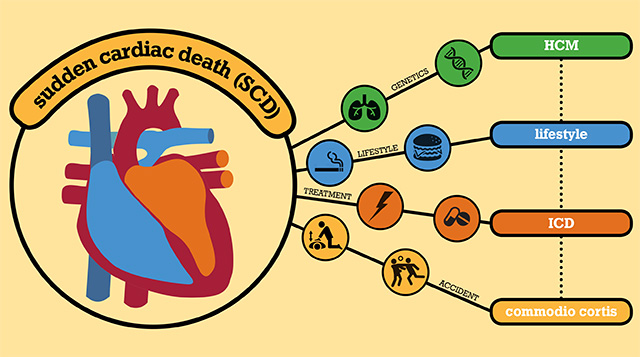

Sudden Cardiac Death

www.rsimmanuel.comSudden cardiac death

Sudden Cardiac Death

www.rsimmanuel.comSudden cardiac death